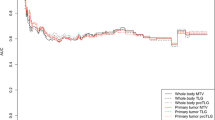

Multivariable CoxPH models demonstrated superior prognostic power when trained with features quantifying response heterogeneity in all individual lesion-ROI in DLBCL (C-index = 0.84, p < 0.001) and NSCLC (C-index = 0.71, p < 0.001). Prognostic power significantly deteriorated (p < 0.001) when using subsets of lesion-ROI (C-index = 0.78 and 0.67 for DLBCL and NSCLC, respectively) or excluding response heterogeneity (C-index = 0.67 and 0.70). RECIST, PERCIST, and Deauville score could not significantly associate with OS (C-index < 0.65 and p > 0.1), performing significantly worse than the multivariable models (p < 0.001).

Lesion-ROI subgroup analysis

First, to assess the value of using all lesion-ROI for analyzing a subject, multivariable CoxPH models were trained, including all features, for different number of lesion-ROI as input:

All lesion-ROI: all lesion-ROI were assessed.

5 biggest lesion-ROI: the five largest lesion-ROI by volume were assessed, with a limit of two lesion-ROI per organ, as prescribed by RECIST criteria.

1 hottest lesion-ROI: the single lesion-ROI with the highest SUVpeak value was assessed, as prescribed by PERCIST criteria.

Feature subgroup analysis

Second, to assess the need to include change of all lesion-ROI, multivariable CoxPH models were trained with different feature sets, extracted for all lesion-ROI, given as input. (Supplementary Table 1)

All features: Baseline (BL: single timepoint whole patient features on the baseline scans), Follow-up (FU: single timepoint whole patient features on the follow-up scans), Patient-level Response (Response: change in each single-timepoint whole patient feature from baseline to follow-up), and intra-patient heterogeneity features.

Baseline + Follow-up + Patient-level Response (BL + FU + Response): Baseline and Follow-up along with percent change in each single-timepoint whole patient feature from baseline to follow-up.

Follow-up (FU): Only single timepoint whole patient features on the follow-up scans.

Baseline (BL): Only single timepoint whole patient features on the baseline scans.